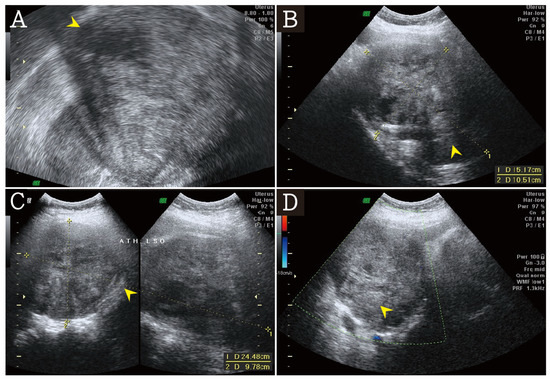

2. Case Presentation